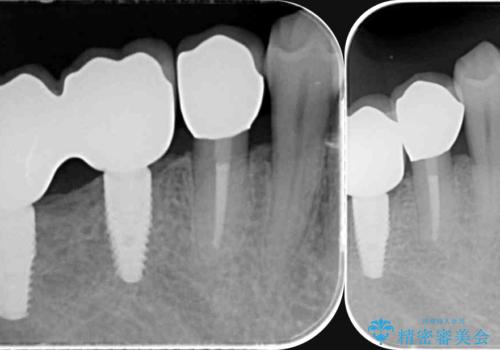

インプラント・ブリッジ補綴を含む、歯周病全顎治療

- 歯が全体的に揺れ始め、恐怖を感じ他院に相談に行ったところ、全体的な歯周病の問題・抜歯の必要性・入れ歯の提案を受け、入れ歯以外の選択肢を希望され来院されました。

全体的な歯周病検査を行い、多数の残すことのできない抜歯の必要な歯を認めたため、残せる歯に対しての徹底的な歯周病治療、失った歯に対しブリッジ・インプラント治療を全顎的に行っていくこととしました。